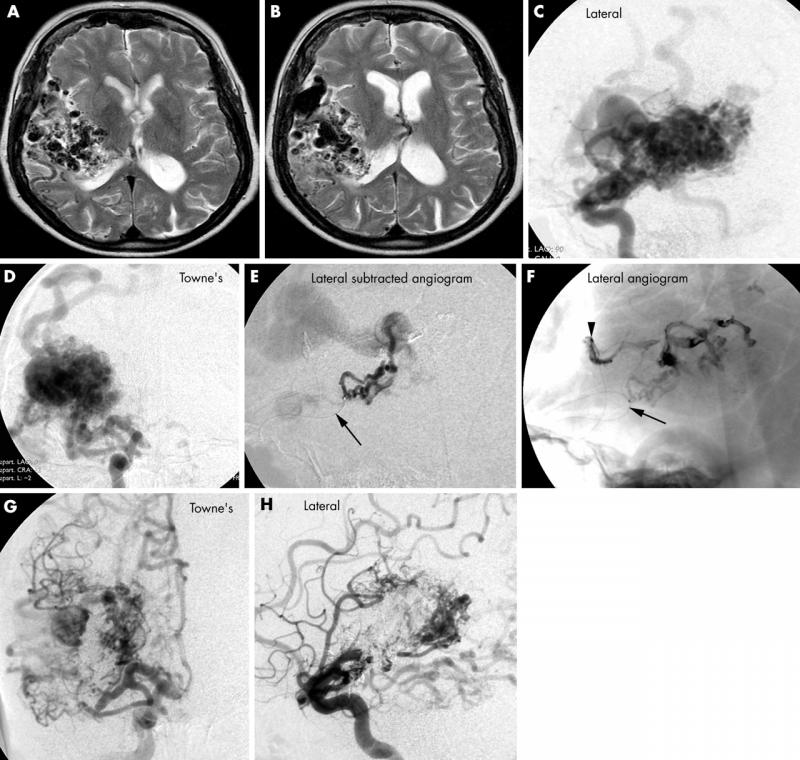

Arteriovenous malformation or AVM is an abnormal connection between veins and arteries, usually congenital This pathology is widely known because of its occurrence in the central nervous system, but can appear in any location.

AVMs may occur in isolation or as a part of another disease (e.g. Von Hippel-Lindau disease or hereditary hemorrhagic telangiectasia). Arteriovenous malformations (AVMs) are the leading cause of stroke in young people

Bleeding from an AVM can be devastating, particularly in the brain. It can cause severe and often fatal strokes. If a cerebral AVM is detected before a stroke occurs, usually the arteries feeding blood into the nidus can be closed off to avert the danger.